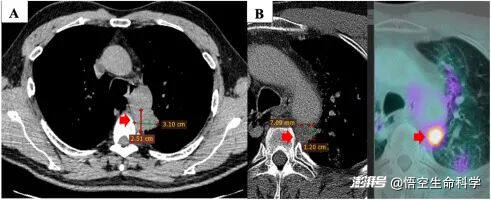

▲首次診斷時對原發(fā)腫瘤進(jìn)行CT掃描檢查(A)。

▲一線治療一年后病情進(jìn)展:原發(fā)腫瘤(A)、左鎖骨上淋巴結(jié)(B)。